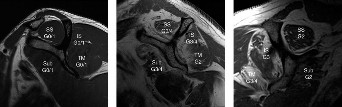

The correct answer is (B). The Snyder classification of SLAP tears is the first widely used classification systems for SLAP tears and consists of types I to IV (see Fig. 2–22A–B and Table 2–3). In type I tears (Answer A), there is fraying of the glenoid edge of the superior labrum, but the biceps tendon and superior labrum are both firmly attached to the biceps anchor and glenoid edge. In type II tears (Answer B), the biceps tendon and the superior labrum are detached from the superior glenoid edge and biceps anchor. In type III tears (Answer C), there is a bucket-handle tear of the superior labrum, but the remainder of the superior labrum and biceps tendon remain firmly attached to the glenoid rim and biceps anchor. In type IV tears (Answer D), there is a bucket-handle tear of the superior labrum that extends into the biceps tendon with extension of parts of the labral flap or biceps tendon into the joint space, and the remainder of the labrum and biceps tendon remain firmly attached to the glenoid rim and biceps anchor. Type V tears (Answer

Figure 2–22(A–B) Snyder classification of rotator cuff tears in cartoon and arthroscopic views. (From Mileski RA, Snyder SJ. Superior labral lesions in the shoulder: pathoanatomy and surgical management. J Am Acad Orthop Surg. 1998;6(2):121–131.)